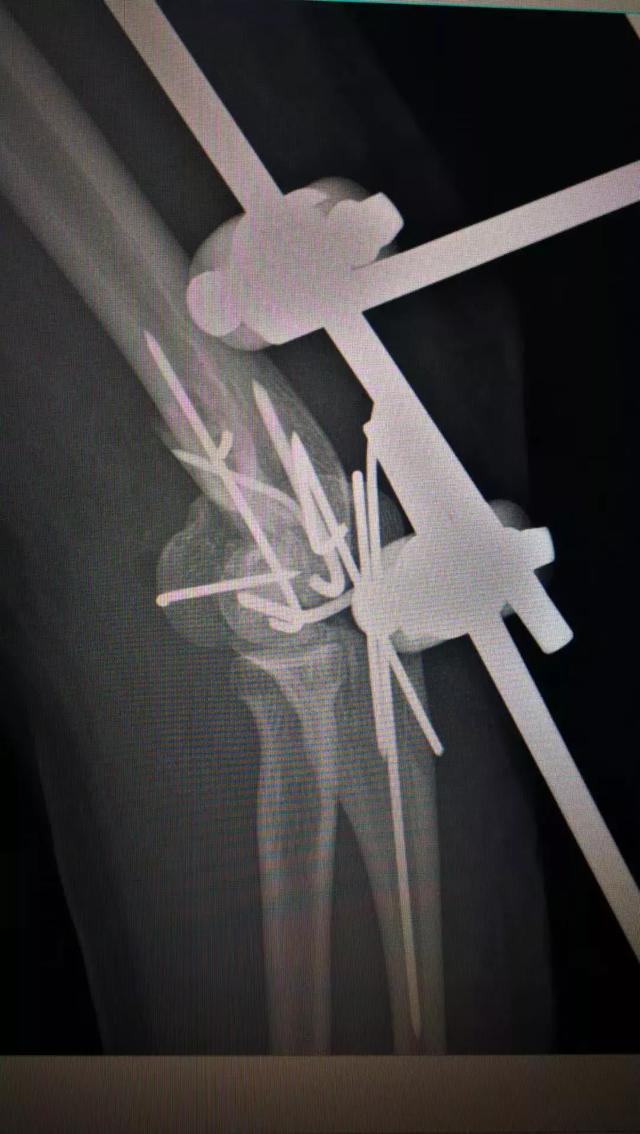

于是,张主任带领团队清晨急诊给她做了肘部扩创、血管神经肌腱关节囊探查修复、局部皮瓣转移、肱骨骨折尺骨骨折切开复位内固定+骨折外固定关节外固定架固定、食指近节指骨骨折內固定术。此类手术需要医生极为细致与耐心,还要在术中不断地评估决策,为伤员的短期与长期利益抉择出最佳方案。

.术前术后对比图